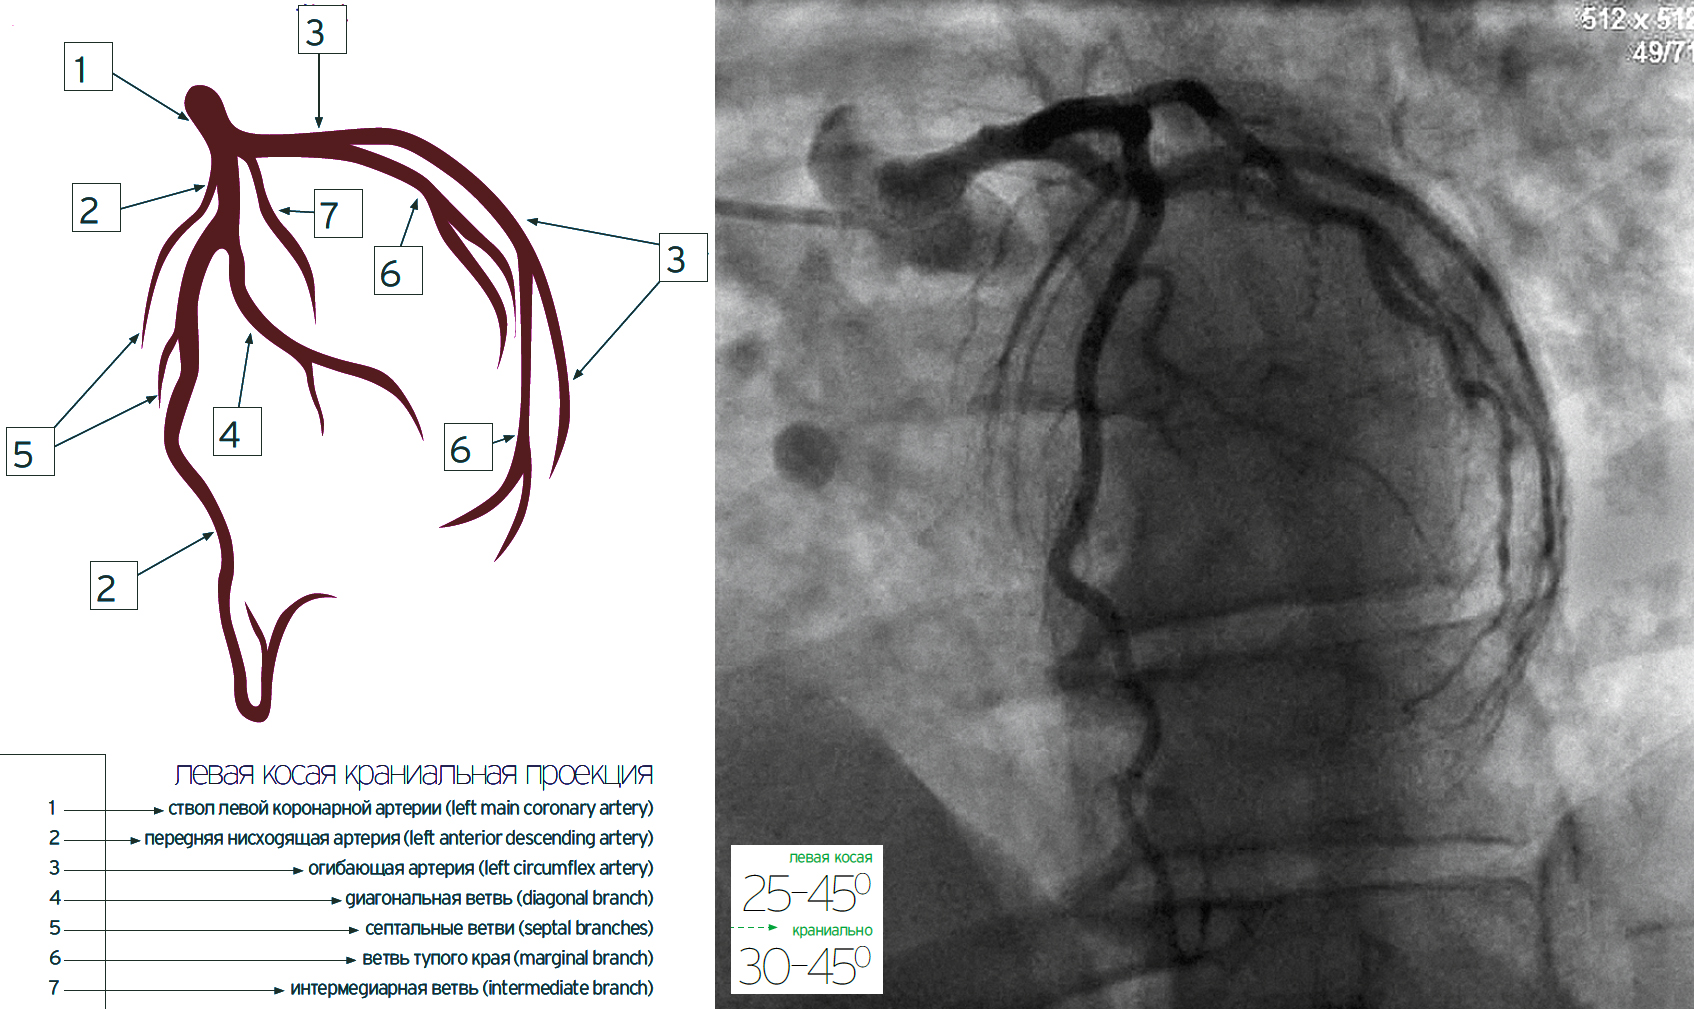

Оа артерия

Оа артерия 114 фото